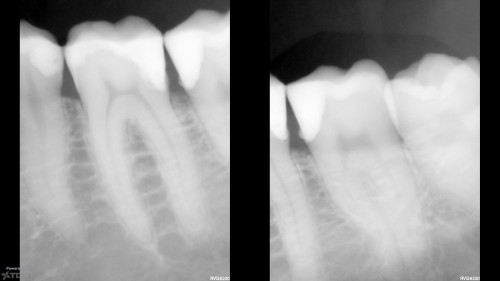

First ortho extrusion courtesy of Scott Weed.

Patient presents for experimentation. 😀 Scott helped me out with this case and sent detailed instructions […]